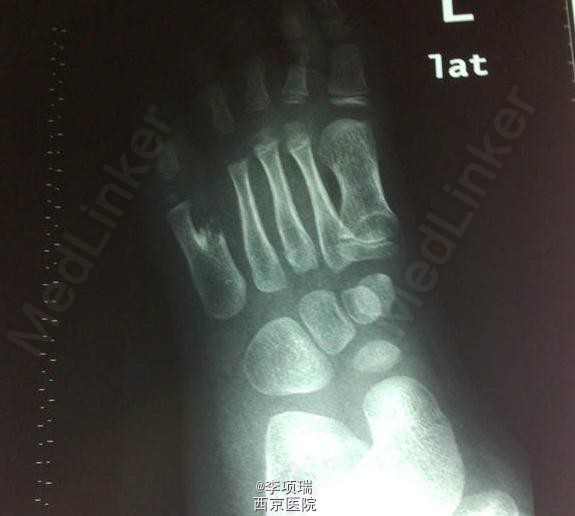

脚趾多趾病例1例

多趾

5岁女童,左足第五趾多趾,行多趾切除+肌腱移位术。